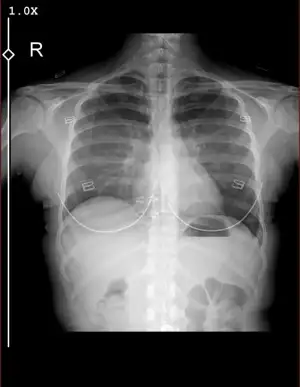

Merhaba bugün kadın hastalıkları ve doğum bölümüne gittim rahim ağzında yara var diye ve bana yakma önerdiler bi kaç test yaptılar anestezi için ve sonuçları pazartesi göstericem ama sonuçlar çıktığı için merak ediyorum aranızda anlayan veya doktor olan biri varsa cevaplayabilirmi rica etsem?

IMG_8035.webp32,3 KB · Görüntüleme: 115

IMG_8035.webp32,3 KB · Görüntüleme: 115 -

IMG_8036.webp32,2 KB · Görüntüleme: 112

IMG_8036.webp32,2 KB · Görüntüleme: 112 -

IMG_8037.webp20,9 KB · Görüntüleme: 115

IMG_8037.webp20,9 KB · Görüntüleme: 115 -

IMG_8038.webp21,8 KB · Görüntüleme: 104

IMG_8038.webp21,8 KB · Görüntüleme: 104 -

IMG_8039.webp21,3 KB · Görüntüleme: 108

IMG_8039.webp21,3 KB · Görüntüleme: 108 -

IMG_8040.webp18 KB · Görüntüleme: 105

IMG_8040.webp18 KB · Görüntüleme: 105 -

IMG_8041.webp20,9 KB · Görüntüleme: 101

IMG_8041.webp20,9 KB · Görüntüleme: 101 -

IMG_8042.webp40,6 KB · Görüntüleme: 115

IMG_8042.webp40,6 KB · Görüntüleme: 115